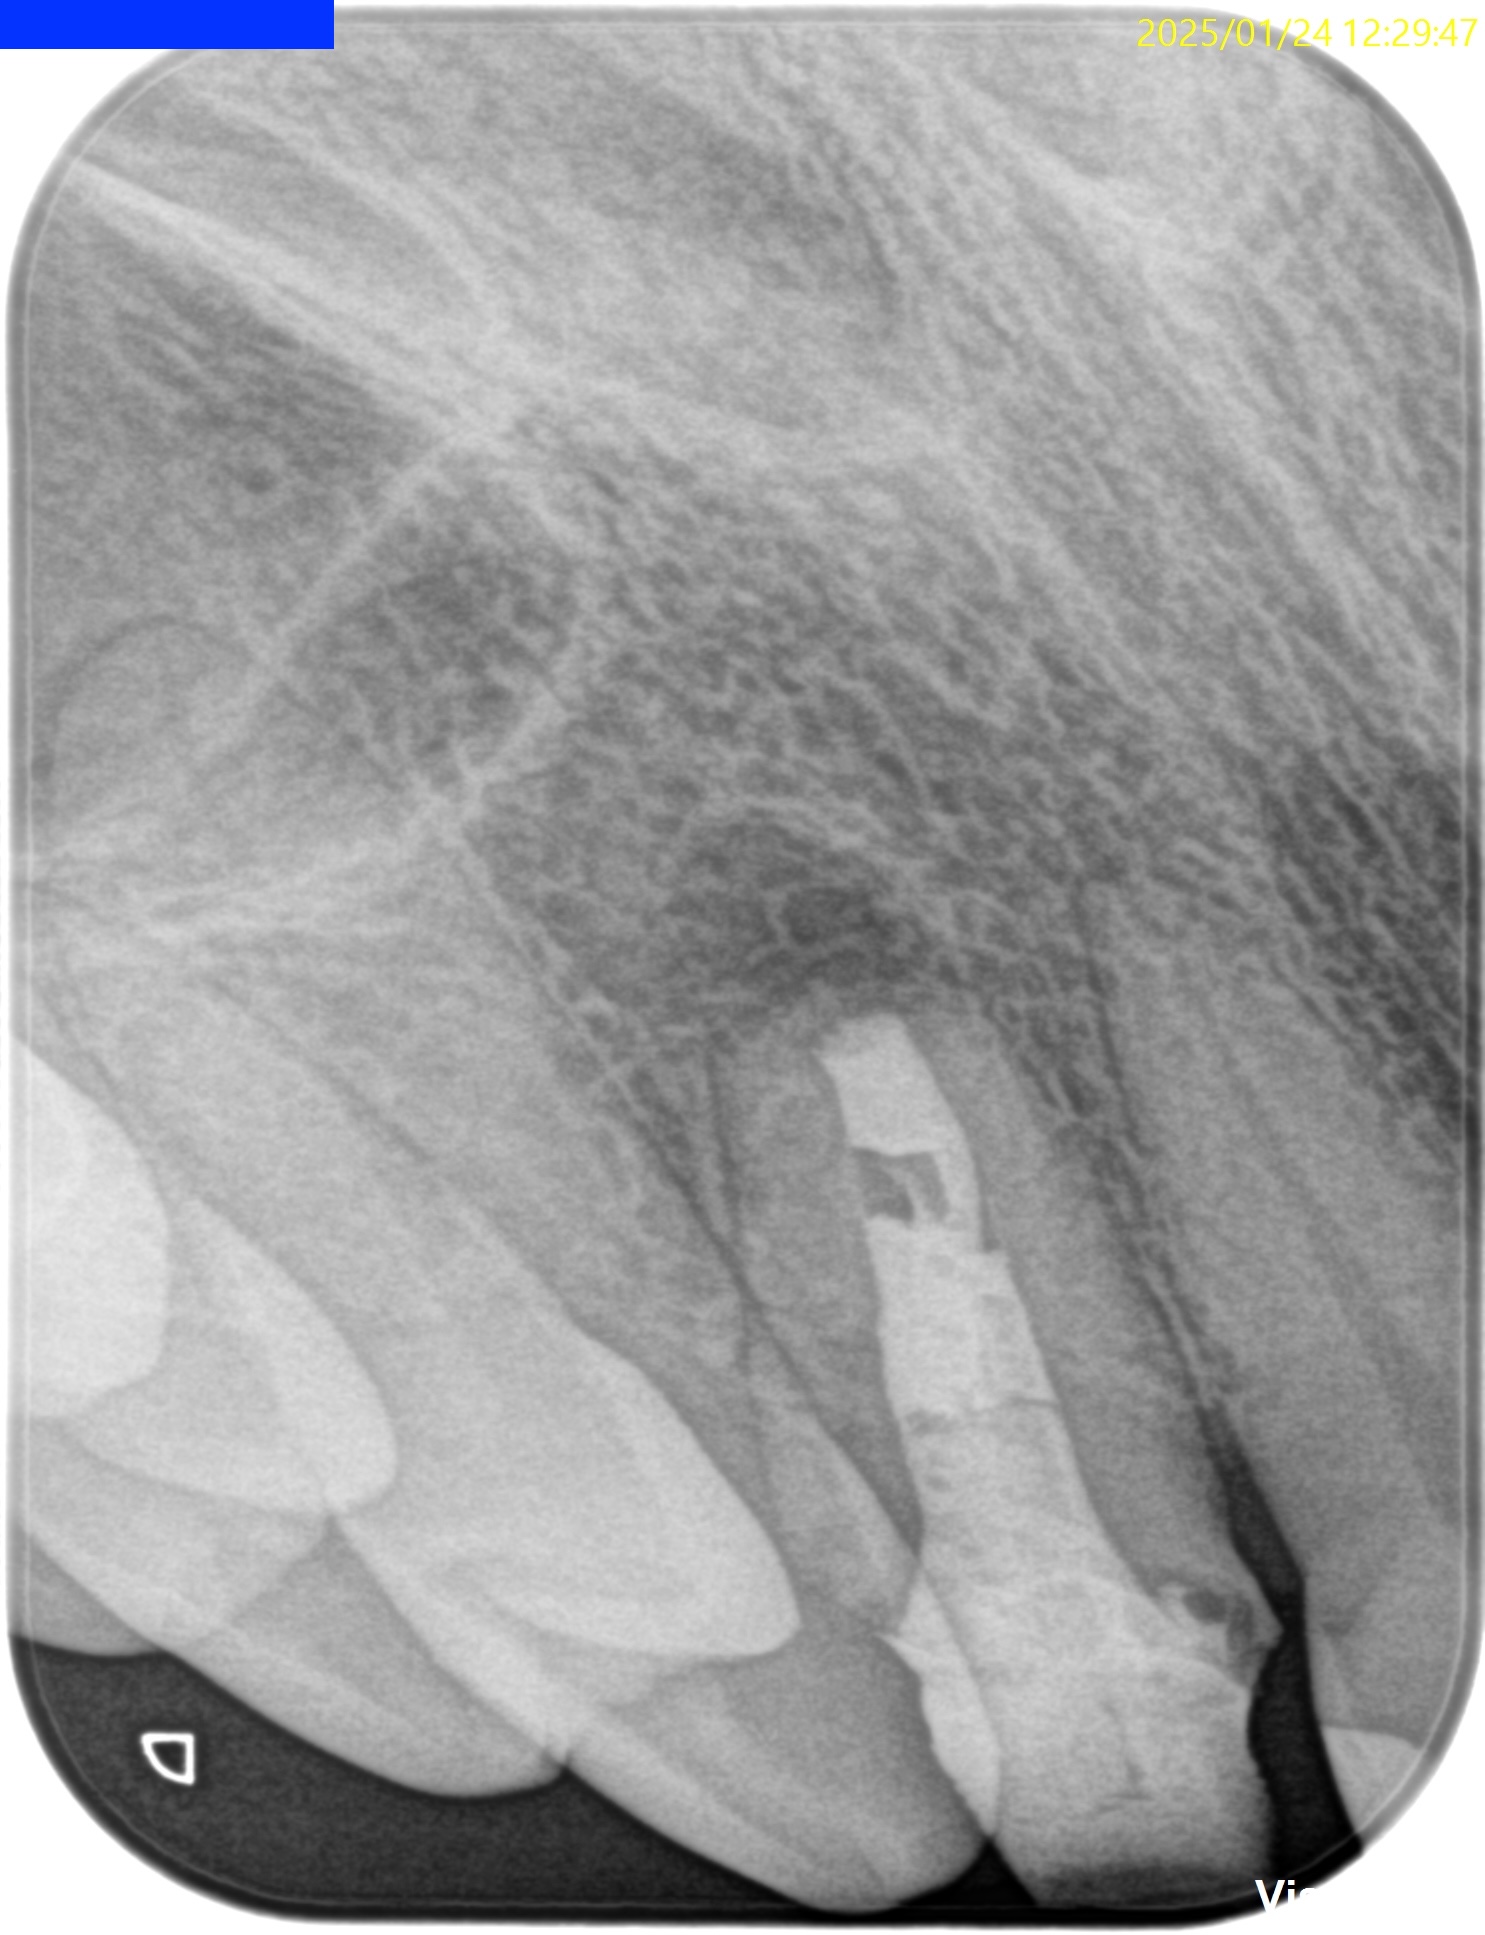

Pre-op Endo test(2025.1.24)

根尖が既に開いており、圧痛があったことから治療は再根管治療ではなく、歯根端切除術であるということがわかる。

クラウンのマージンより11.5mm下方に#7のApexはあり、そこを3mm切断するには頬舌的に4.4mmの幅があるということがわかる。

Pulp Dx: Previously treated

Periapical Dx: Asymptomatic apical periodontitis

Recommended Tx: Core build up w Fiber Post⇨Apicoectomy

術後にPA, CBCTを撮影した。

気泡が逆根管充填材に混入したが、問題はないだろう。